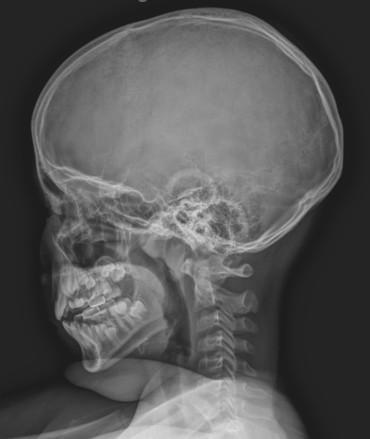

거북목이나 척추측만증 등으로 척추 정렬이 무너지면 성장판에 균등한 자극이 전달되지 않는다. 스마트기기 사용이 늘어난 환경에서는 이러한 자세 이상이 더욱 흔하다. 따라서 단순히 손 X-ray만으로 성장 검사를 끝내지 않고, 목·등·허리·골반을 포함한 전체 척추 정렬을 함께 확인하는 것이 중요하다.

성장 관리에서 핵심 부위로 꼽히는 경추 2번(축추, Axis)은 신체 중심을 지탱하는 구조로, 틀어지면 전신 정렬이 무너지고 신경 기능에도 영향을 줄 수 있다. 이와 연결된 턱관절(TMJ)의 균형이 흐트러지면 경추에도 변형이 생길 수 있어 턱관절과 척추를 동시에 교정하는 치료가 권장된다.